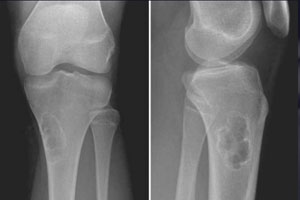

- рентгенографии — проводится с целью выявления онкообразования и определения его особенностей;